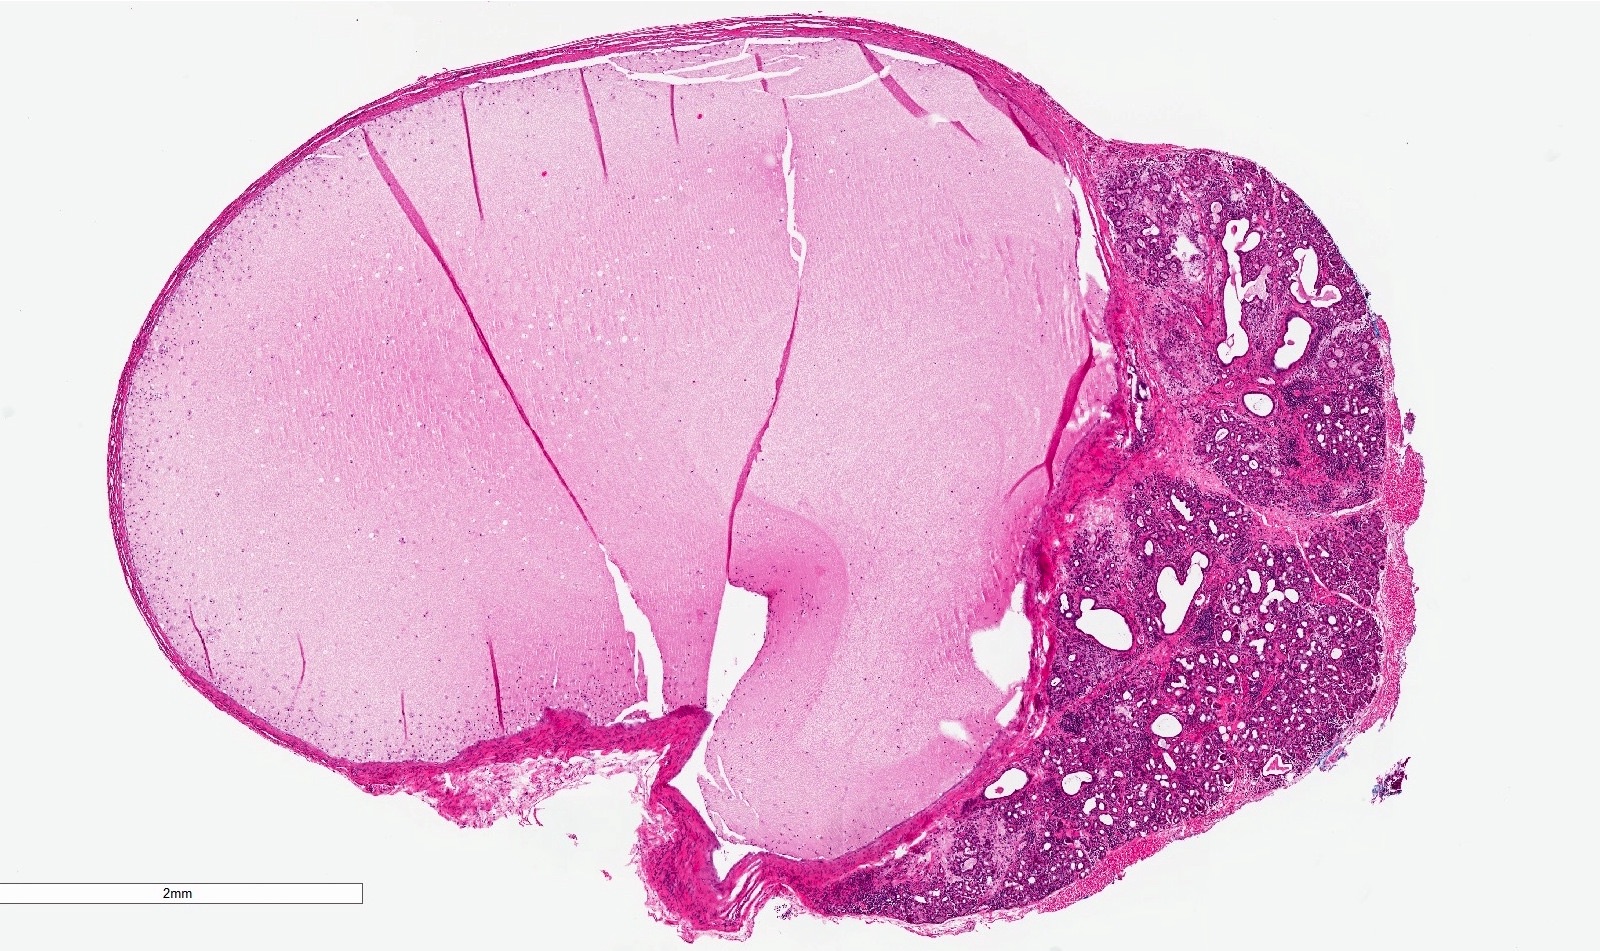

Microscopic (histologic) description

- If removed intact

- Pseudocyst cavity containing mucin, abundant epithelioid foamy histiocytes (muciphages), neutrophils and granulation tissue (Acta Histochem 2014;116:40)

- If removed ruptured

- Fragments of granulation tissue containing epithelioid foamy histiocytes (muciphages) and neutrophils, may see mucinous material (Acta Histochem 2014;116:40)

- Removed salivary gland parenchyma showing obstructive changes

- Acinar atrophy, ductal dilatation with periductal hyalinization, interstitial lymphoplasmacytic infiltrate and interstitial fibrosis at late stage (J Oral Maxillofac Surg 2008;66:2050)

- May see ruptured feeding salivary duct with squamous metaplasia (J Oral Maxillofac Surg 2008;66:2050)

- Long standing lesions organize into fibrosis resembling a fibroepithelial polyp (Acta Histochem 2014;116:40)

- No epithelial cyst lining, may see overlying surface oral mucosa with variable atrophy in superficial mucoceles (J Oral Maxillofac Surg 2011;69:1086)

Microscopic (histologic) images